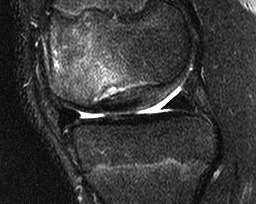

MRI

MRI demonstrates large OCD with fluid completely separating bone on all views

MRI demonstrates large OCD with fluid completely separating bone on all views